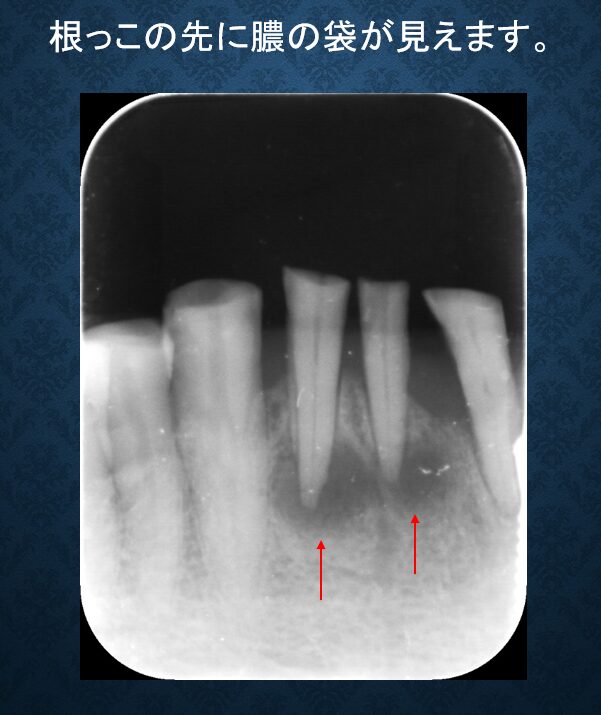

レントゲンを撮ってみると様々な問題点が浮き彫りになりました。

一番の問題点は当院で扱っていないメーカーのインプラントがTさんのお口の中に入っていた事でした。インプラントメーカーは海外から国産のものまで多数存在し、各メーカーによって様々なパーツの形状や使用器具等の規格が異なるため(互換性がないため)、Tさんに入っているインプラントに今後もし何かトラブルがあった時には、私には対応できない事になりご迷惑をおかけすることになってしまいます。どこのメーカーか書籍で調べましたが結局似たような形状のメーカーが多く区別がつかなくて、わかりませんでした。